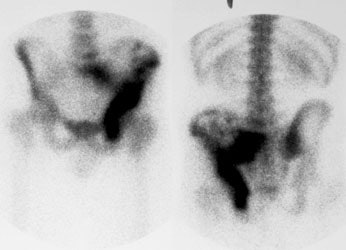

"Superscan" in patient with prostate cancer: A "Superscan" occurs in a patient with widespread osteoblastic bone metastatses. There is diffuse, intense skeletal uptake of the tracer with absent renal and background activity. |

Ewings sarcoma of the pelvis: The bone scan demonstrates extensive, intense tracer uptake involving the left iliac wing, extending into the ischium and left sacrum. CT scan revealed a mixed, but predominantly sclerotic lesion involving the bone with an associated soft tissue mass. Note that the sacrum fails to demonstrate a CT abnormality. The T2 weighted images from the patients MR exam more clearly defines the lesion. Sacral involvement is clearly evident (white arrows) and there is also a large soft tissue component. |